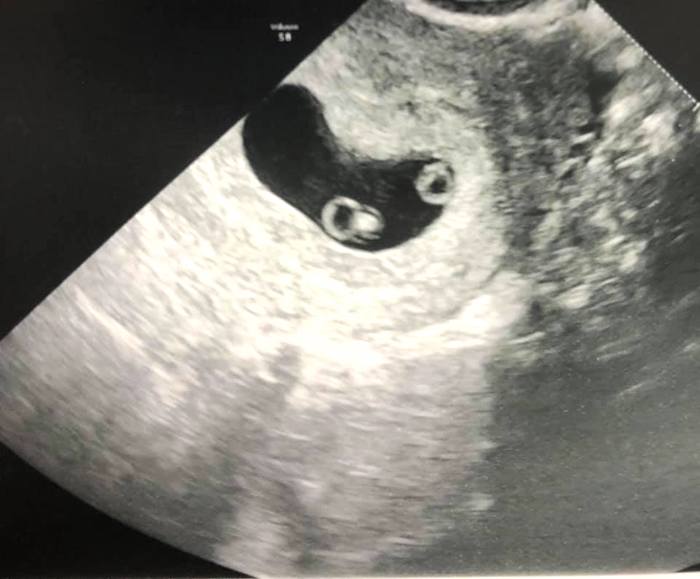

Early Twin Ultrasound at 7 Weeks

The earliest your doctor would likely order an ultrasound confirming twins would be 4 weeks pregnant. But unless you are going through fertility treatments, doing an ultrasound before 6 weeks isn’t very common, with the exception of complications. Women who are going through fertility treatments or have early complications may be able to have an early twin ultrasound at 4 or 5 weeks pregnant and find out they are pregnant with twins.

At four to five weeks after a pregnant woman’s last period the ultrasound commonly shows a small collection of fluid within the lining of the uterus that represents the early development of the gestational sac. At about five and a half weeks after a pregnant woman’s last period the ultrasound typically shows a gestational sac and within it we can see a 3-5 mm bubble-like structure, which is the yolk sac. At approximately six weeks after a pregnant woman’s last period, we can see a small fetal pole, one of the first stages of growth for an embryo, which develops alongside the yolk sac.

Yes! You’d need to have an ultrasound at 7 weeks to confirm a twin pregnancy. Your twin belly at 7 weeks may not look like much of a belly at all, so getting in to your doctor for an ultrasound is key to find out if you’re really having twins.